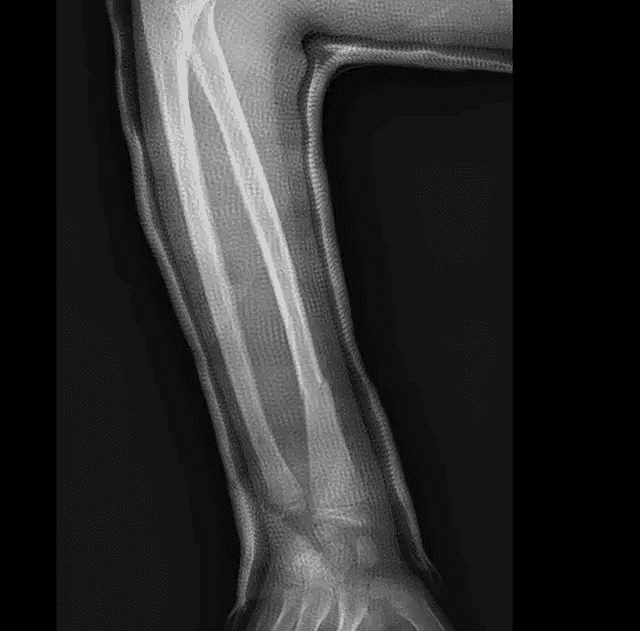

Suivi évolutif de la fracture du radius à 15 jours d'intervalle avec constitution d'un cal osseux à 1 mois sans déplacement secondaire associé.

Suivi à 2 semaines